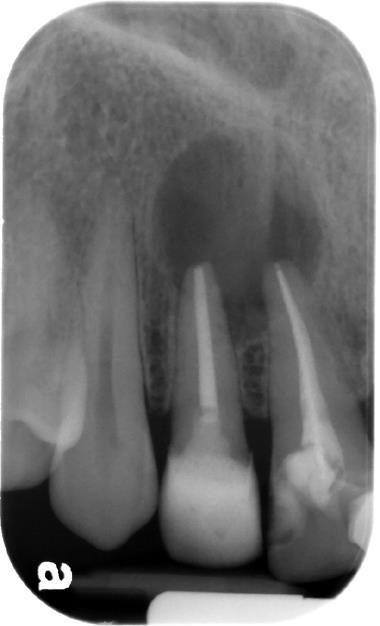

Cyst From Apex Of Non-Vital Incisor Tooth

??

Case 21 Diagnosis

Radicular cyst